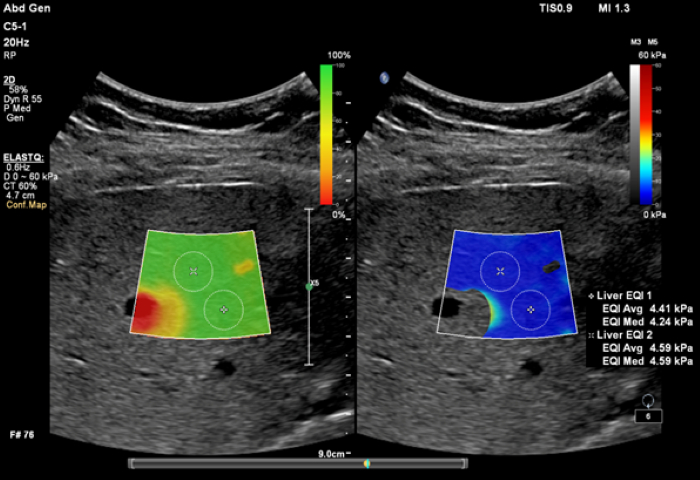

ElastQ Imagingは、大きな関心領域(ROI)で組織の硬さをリアルタイムでカラーコード化する定量的評価方法です。リアルタイムに肝組織の硬さを迅速に評価し、複数のサンプルポイントで定量評価を行うことができます。ElastQ Imagingには、保存済みの画像も測定できる機能が用意されています。Confidence map表示では、適切にShear Waveが伝搬されている領域で測定していること確認できるよう、インテリジェント解析がされています。Confidence map表示とStiffness map表示を組み合わせて使用することで、シアウェーブ測定の確度が向上します。2つのマップを並列表示することで、データの計測を相互に関連付けて行うことができます。